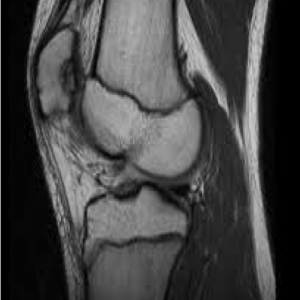

RNM rodilla